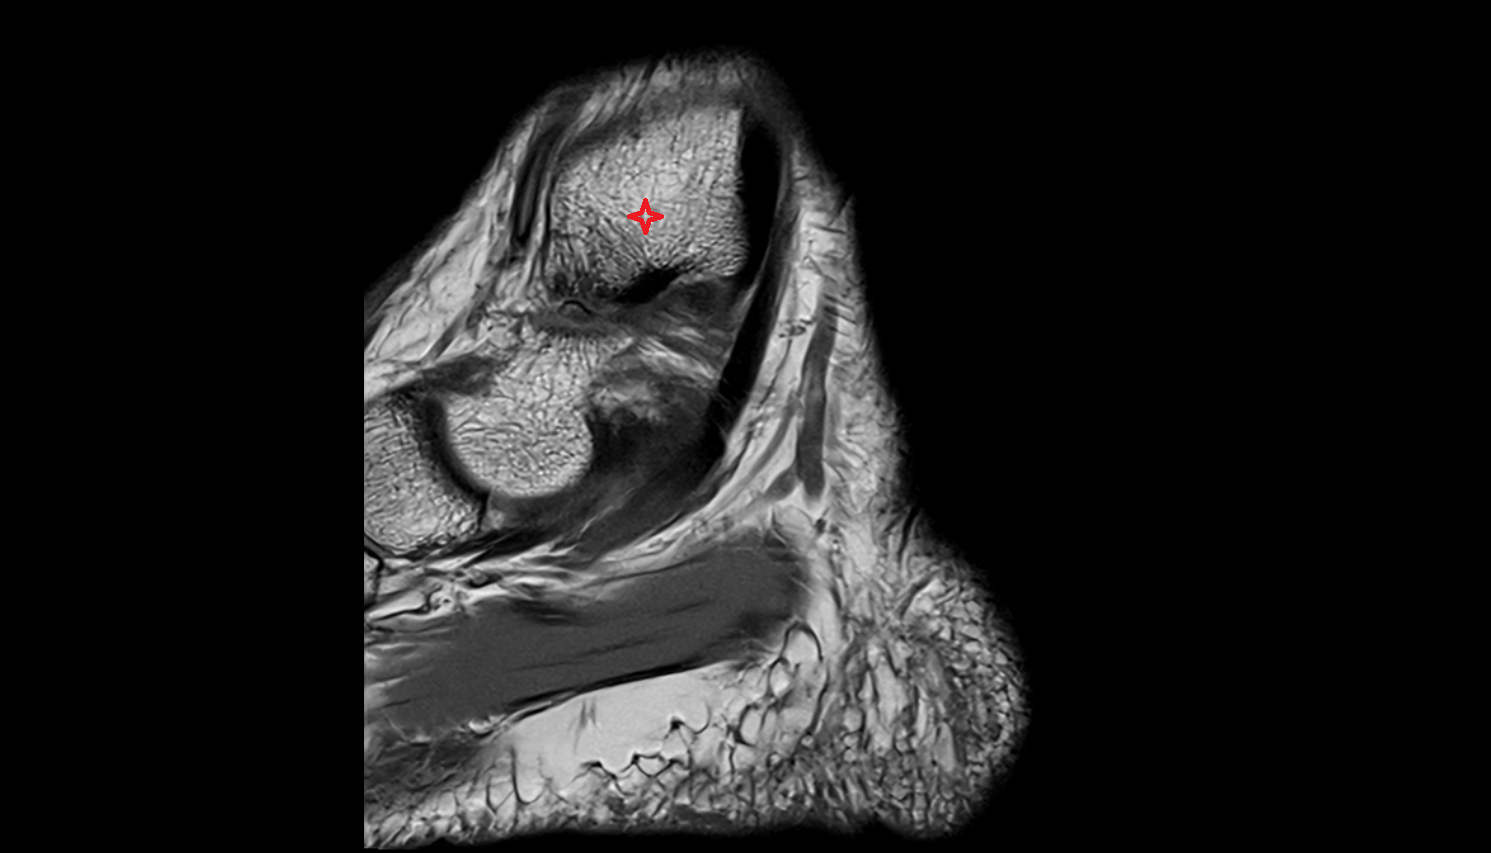

- Knee Joint